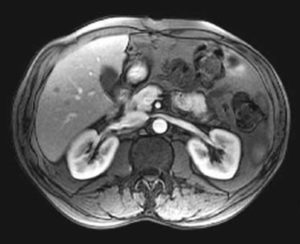

Фото МРТ надпочечников

Андростерому можно диагностировать, основываясь на клинических проявлениях, а также на результатах лабораторных и инструментальных исследований. Эти методы не только подтверждают предварительный диагноз, но и помогают отличить заболевание от других патологий, которые также могут вызывать вирилизацию. Для этого применяются следующие методы:

- МРТ. Данный метод сканирования позволяет определить точные размеры и расположение опухоли.